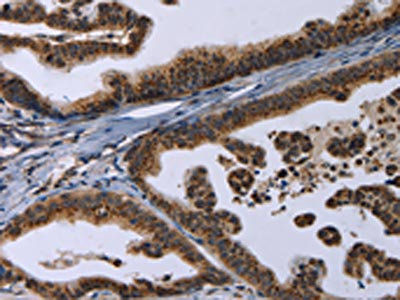

The image on the left is immunohistochemistry of paraffin-embedded Human gastic cancer tissue using CSB-PA174492(REG3A Antibody) at dilution 1/20, on the right is treated with synthetic peptide. (Original magnification: ×200)

The image on the left is immunohistochemistry of paraffin-embedded Human brain tissue using CSB-PA174492(REG3A Antibody) at dilution 1/20, on the right is treated with synthetic peptide. (Original magnification: ×200)